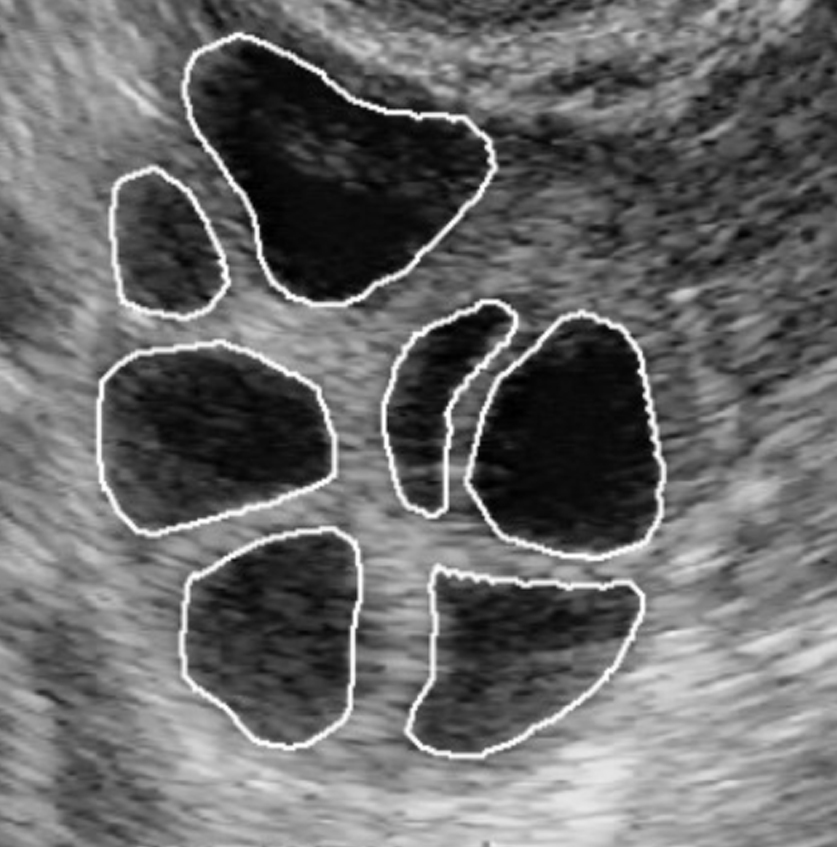

Prenatal Ultrason

Prenatal ultrason, gebelik sürecinde anne karnındaki bebeğin gelişimini, büyü...